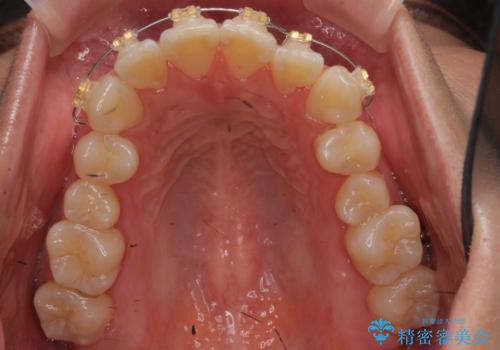

上のワイヤー矯正を半年ほど行い反対咬合を改善してから、上下インビザライン治療を行いました。